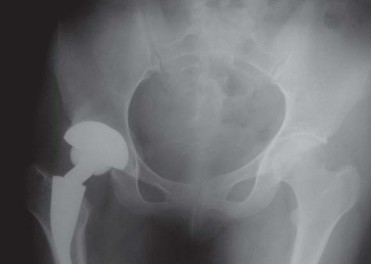

تُقدم تصاميم الجذع القصير خيارًا محافظًا لاستبدال مفصل الفخذ الكلي، حيث تحافظ على العظم والأنسجة الرخوة، وتُعد مناسبة للمرضى الشباب والنشطين الذين يعانون من التهاب مفصل الفخذ الموهن. يُنسب مفهوم جراحة استبدال مفصل الفخذ الكلي التي تحافظ على عنق الفخذ إلى مايكل فريمان. وقد اقترح ليو وايتسايد وتاونلي مفهومًا مشابهًا يدعو إلى الحفاظ على عنق الفخذ باستخدام جذوع تقليدية. أظهر وايتسايد وزملاؤه في دراسة على الجثث أن الحفاظ على 50% أو أكثر من عنق الفخذ يساعد في مقاومة القوى الالتوائية في الجذع المثبت قربيًا. كما أظهرت دراسة أجراها جاستي وزملاؤه على الكلاب، باستخدام جذوع مثبتة قربيًا مع جذع بعيد مصقول، أن المكون الديافيزي للجذع يوفر ثباتًا أوليًا ولكنه ليس ضروريًا لاستقرار الزرعة على المدى الطويل بمجرد تحقيق الاندماج العظمي القريب. وقد أدى ذلك إلى تطوير جذوع قصيرة تثبت في منطقة الميتافيزال.

تم توثيق نتائج ناجحة باستخدام جذوع مخروطية مع زرعات تحميل الميتافيزال. إن الزرعات القصيرة المثبتة في الميتافيزال تحافظ على العظم، ويمكن زرعها باستخدام نهج جراحي طفيف التوغل، ويمكن استخدامها مع مجموعة متنوعة من أسطح الاحتكاك. مقارنة بجذوع الفخذ التقليدية، فإن زرعات الجذع القصير أكثر فسيولوجية، أي أنها توفر تحميلًا قريبًا، ولا تسبب ألمًا في الفخذ، ويسهل مراجعتها إلى استبدال مفصل الفخذ التقليدي. ومن ثم، فإن زرعات التحميل الميتافيزي القصير تعمل كجسر بين جراحة إعادة تسطيح المفصل والجذوع غير الإسمنتية القياسية، وهي مناسبة للمرضى الشباب الذين يعانون من التهاب المفاصل ولديهم عظم جيد النوعية.

METHA هو جذع قصير معياري يعتمد على مفصل Mayo الناجح للغاية. يجمع الزرع بين ثلاث ميزات مهمة: البناء المعياري، والتثبيت الميتافيزي، والتحميل القريب مع الحد الأدنى من حجم الجذع والطلاء المحيطي، مما يؤدي إلى تثبيت بيولوجي. ويحتوي على جميع الميزات المطلوبة من زرع فخذ حديث، وهي: الحفاظ على العظم، والتحميل الفسيولوجي لعنق الفخذ وميتافيزال الفخذ القريب، والقدرة على استعادة ميكانيكا مفصل الفخذ دون إطالة الطرف، وإمكانية الوصول الجراحي الأقل توغلاً.

تصميم مفصل METHA

يُعد METHA جذعًا معياريًا، يُثبت في الميتافيزال، وغير إسمنتي. يتميز بتصميم مستوحى من مفصل Mayo الناجح، ولكنه يتفوق عليه في عدة جوانب:

- شكل شبه منحرف واسع: يوفر ثباتًا أوليًا ممتازًا مع الحفاظ على العظم الإسفنجي.

- مادة الصنع والطلاء: يتكون من جذع مخروطي مزدوج من التيتانيوم، مغطى بالكامل بطلاء التيتانيوم النقي المسامي الدقيق (بلازمابور) مع طبقة رقيقة من فوسفات الكالسيوم ثنائي الهيدرات. هذا الطلاء يعزز التوصيل العظمي ويؤدي إلى اندماج عظمي مبكر، مما يوفر ثباتًا ثانويًا.

- الطرف البعيد غير المطلي: يعمل كدليل للزرعة على طول القشرة الظهرية الجانبية، مما يعزز الثبات الأولي العالي. لا يشارك طرف الجذع بشكل كبير في نقل الحمل، بل يعزز الثبات المحوري.

- وحدات الرأس والعنق المعيارية: تتوفر تسعة محولات للعنق مصنوعة من الكوبالت والكروم، بزوايا عنق الفخذ 130، 135، 140 درجة، وزوايا دوران 0، 7.5 درجة أمامية، و7.5 درجة خلفية لكل زاوية. تتوفر الجذوع بسبعة أحجام من 0 إلى 6. تسمح هذه المحولات المعيارية بتحسين ميكانيكا مفصل الفخذ لكل مريض على حدة دون إطالة الطرف.